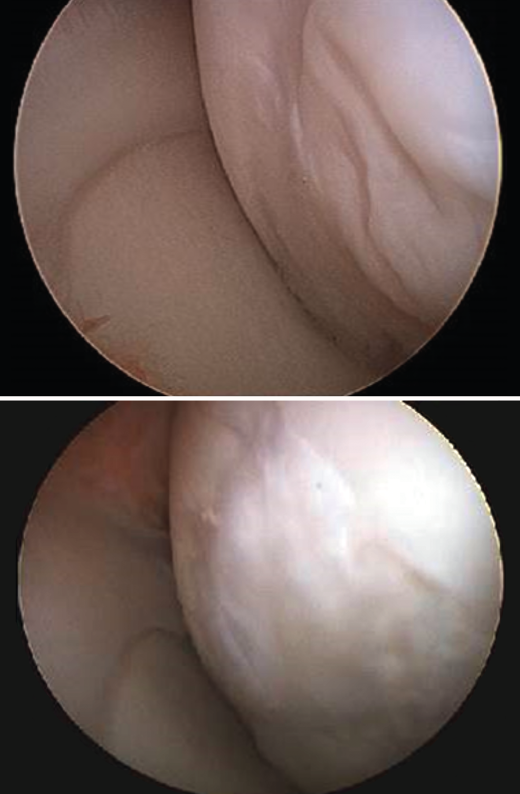

In 5 cases a biopsy of the regenerated tissue could be obtained two years after implantation. The histological study revealed chondrocytes surrounded by a cartilaginous matrix, distributed in clusters, and with a columnar distribution in some areas (Figure 9).